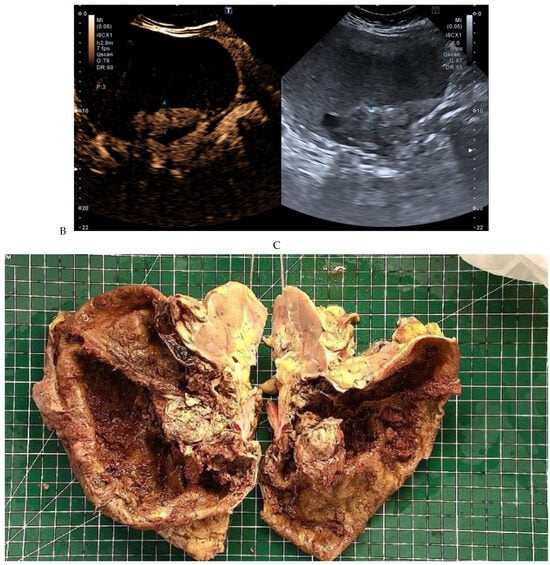

Figure 5.

Clear cell renal cell carcinoma in the right kidney of a 52-year-old-man. (A) Coronal T2-weighted fast SE image shows a large heterogeneous mass with areas of high signal intensity compared with renal parenchyma. Transverse in-phase (B,C) opposed-phase MR images show a subtle signal loss on the opposed-phase image. (D) The ADC map is heterogeneous with predominant areas of restriction of tumor diffusion. Transverse gadolinium-enhanced T1-weighted gradient-echo spoiled MR images in (E) corticomedullary, (F) nephrographic, (G) and delayed phase images show intense and rapid peripheral enhancement during the arterial and nephrographic phases followed by a rapid washout of contrast on the delayed phase. Central necrotic areas do not enhance. (H) Macroscopic view of the lesion after radical nephrectomy. The lesion appears heterogeneous. Courtesy of Pr S. Ferlicot, Department of Pathology, Bicêtre Hospital.